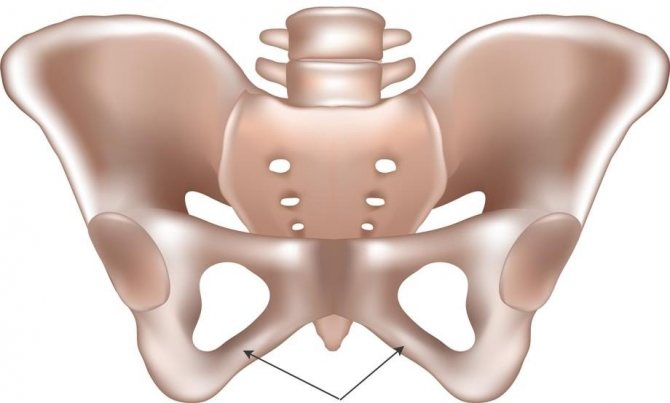

Седалищная кость достаточно тонка и состоит из двух частей – изгибающихся под углом ветвей и непосредственно тела, которое образует задний и отчасти нижний отделы ветлужной впадины и достаточно плавно переходит в верхнюю часть ветви седалищной кости.

Что касается ветви седалищной кости, то она имеет небольшое шероховатое утолщение (так называемый седалищный бугор) и нижней частью в передних отделах соединена с нижней ветвью лобковой кости.

Седалищные кости являются парными в человеческом организме. В составе тазовых костей они симметричны с правой и левой стороны. Выделяется две их главные части: тело и ветвь.

Тело кости вместе с подвздошной костью формирует вертлужную впадину. Путем сочленения ее с головкой бедренной кости происходит формирование тазобедренного сустава, одного из самых крупных в человеческом теле. Другое название тела кости – задненижний отдел.

На границе между нижним участком тела кости и ее ветвью на задней выгнутой поверхности располагается седалищный бугор, представляющий собой утолщение, поверхность которого слегка шероховата. К нему прикреплена крестцово-бугорная связка. Зона между бугром и суставной границей вертлужной впадины – это место расположения седалищно-суставной борозды. Она представляет собой своеобразное ложе в форме полумесяца с четкими контурами, где располагается внутренняя запирающая мышца.

На задней части тела кости присутствует небольшой отросток, который называется седалищной остью. На ней закреплена крестцово-остистая связка. Между седалищной и нижней задней подвздошной остями (выступ на задней части крыла подвздошной кости) присутствует полукруглая выемка, именуемая большой седалищной вырезкой. Она и крестцово-остистая связка формируют большое седалищное отверстие, сквозь которое из таза выходит грушевидная мышца, она при этом заполняет отверстие не до конца. В результате снизу и сверху этой мышцы в большом отверстии есть щели.

Между остью седалищной кости и ее бугром имеется малая седалищная вырезка – это выемка, которая участвует в формировании малого седалищного отверстия. Сквозь него половой нерв, внутренние половые артерия и вена проходят внутрь полости малого таза.

Ветви седалищных костей, отходя от их бугров, внизу примыкают к нижним ветвям лобковых костей. Это сращение образует запирательное отверстие, своей формой схожее с треугольником со сглаженными углами. Спереди на крае ветви находится задний запирательный бугорок – это небольшое возвышение, куда прикрепляется запирательная мембрана (соединительная пластинка на тазовой кости).

В образовании вертлужной впадины участвуют 3 костных структуры: лобковая, седалищная, подвздошная. Седалищная кость состоит из тела, а также изогнутых под углом ветвей. Строение и анатомия седалищного костного образования:

- Верхняя область ветви имеет образование — запирательный бугорок.

- Ветвью седалищная и лобковая кость срастаются между собой.

- Образования костной ткани тела располагается относительно запирательного отверстия сзади.

Седалищная и лонная костные структуры ограничивают запирательное отверстие, а по его верхнему краю простирается бороздка, усеянная нервно-сосудистой сеткой. Вертлужная впадина имеет центральное расположение на наружной поверхности тазовой кости, а нижняя ее часть прерывается вырезкой.